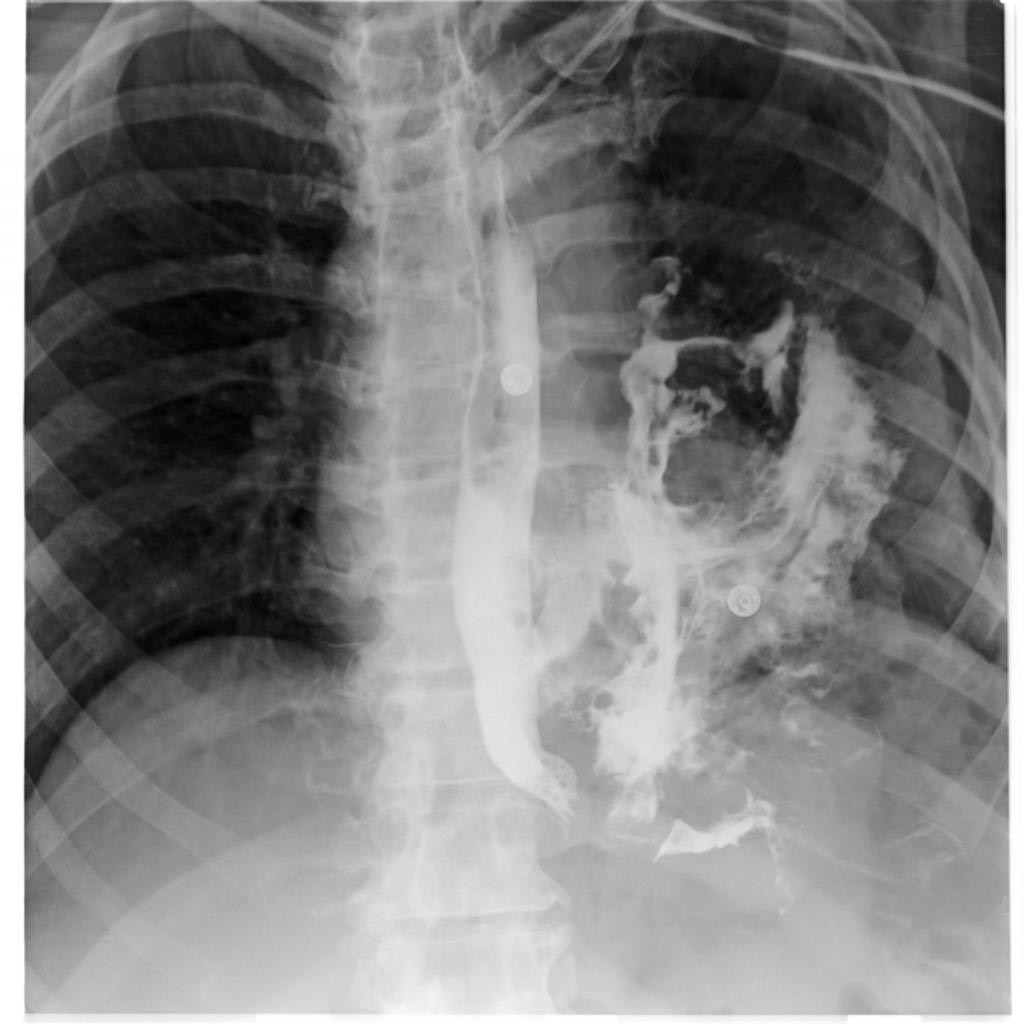

2921. Рентгенологические данные, представленные на снимке

грудной клетки пациента после дренирования плевральной полости по поводу пневмоторакса, развившегося на фоне неукротимой рвоты в связи с алкогольной интоксикацией, наиболее вероятно соответствуют клинической картине